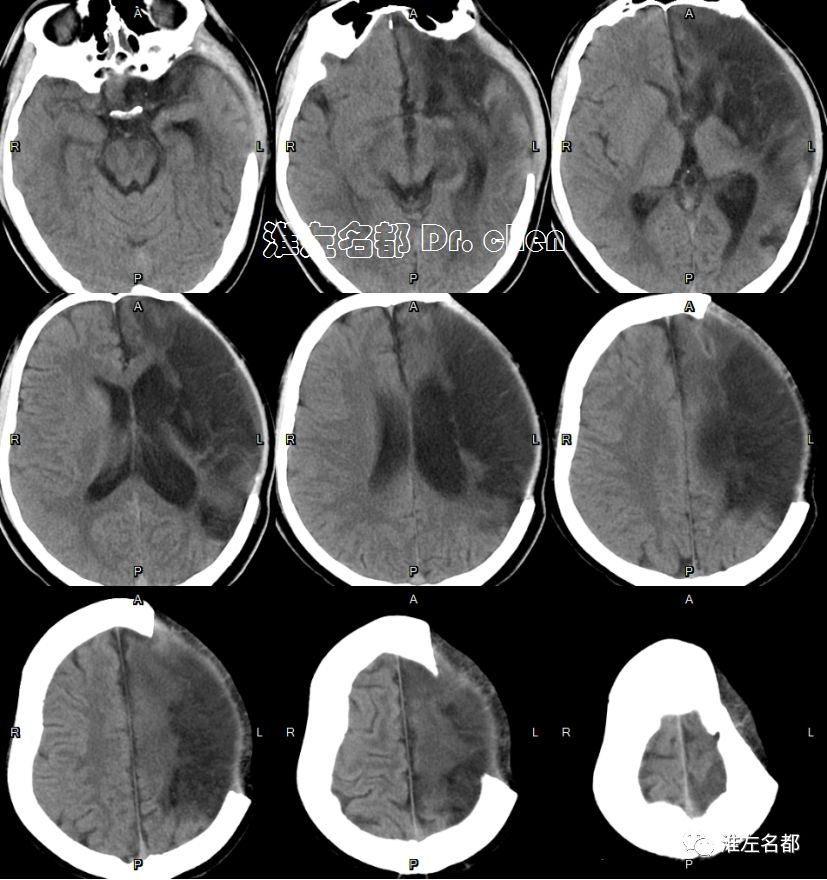

复查多模式CT

2019-9-2 11:47

△头颅CT平扫:左侧去骨瓣减压术后,左侧半球仍有肿胀,中线结构移位较前稍改善。

△头颅CTA:左侧前循环管腔通畅,未见明显狭窄。

△脑CTP:左侧额叶CBV和CBF仍然较对侧显著降低(无复流)

CT

2019-9-9

△头颅CT:左侧去骨瓣减压术后,中线结构居中,侧脑室受压较前改善。

2019-10-22

△头颅CT平扫:左侧去骨瓣减压术后,左侧半球大面积梗死组织坏死软化,左侧侧脑室扩大。

2019-12-20

△头颅CT平扫:左侧去骨瓣减压术后,左侧半球大面积陈旧性梗死软化灶,左侧侧脑室扩大。

2020-1-3

△头颅CT平扫:左侧半球大面积陈旧性梗死软化灶,左侧颅骨修补术后。